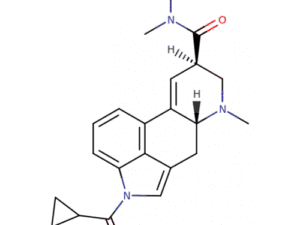

1V-LSD, or 1-valeryl-lysergic acid diethylamide, is a novel lysergamide derivative that closely resembles LSD (Lysergic Acid Diethylamide). This compound is drawing significant interest in the scientific community for its potential to advance our understanding of the pharmacodynamics and pharmacokinetics of psychedelics.

1V-LSD is an invaluable tool for neuroscientific research, particularly in studies focused on understanding the interaction between psychedelics and brain function. Researchers can explore its effects on serotonin receptors, particularly the 5-HT2A receptor, which is crucial to the psychedelic experience.

Due to its potent properties, 1V-LSD is ideal for pharmacological research. Researchers can investigate its bioavailability, metabolic pathways, and potential therapeutic applications, contributing valuable insights to the field of psychopharmacology.